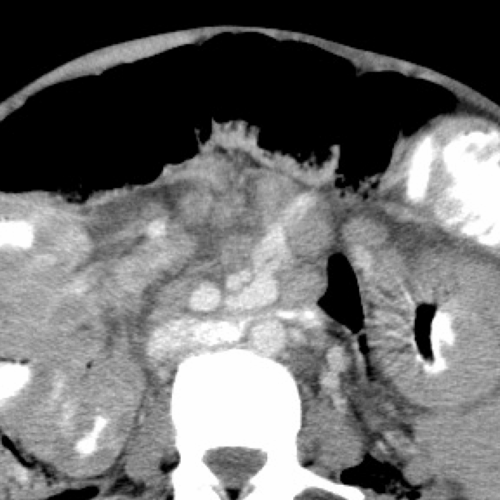

Case 4- Pancreatic pseudocyst with Pseudoaneurysm

A well-defined oval cyst isseen abutting the pancreatic body and tail, suggestive of a pancreatic pseudocyst. The pancreatic duct is minimally prominent. Thecyst is seen anteriorly abutting the stomach wall with resultant diffuse oedematousthickening of the walls of the stomach.A few ill-defined hyperdensitiesare seen within the cyst, suggestive of chronic hemorrhages/ sludge